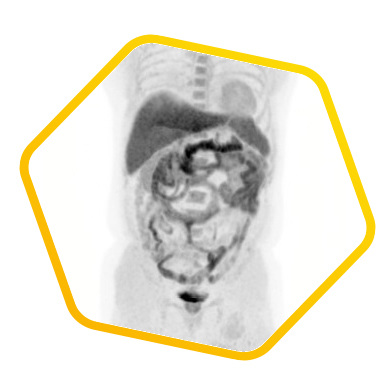

Multiple tracers are used to differentiate biochemical properties of liver lesion – Cancer Associated Fibroblast (Ga-68 FAPI uptake)

[C-11] Acetate and [F-18] FDG for hepatocellular carcinoma cellular differentiation (well and poorly differentiated)

![]() [F-18] FDG |

![]() [C-11] Acetate |

![]() [Ga-68] DOTATATE |

![]() [Ga-68] FAPI |